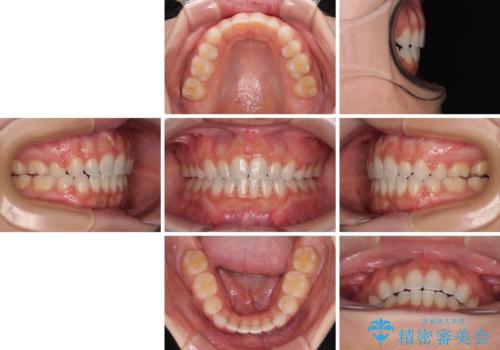

前歯のデコボコとクロスバイト ワイヤー装置での抜歯矯正

スペースを閉じるために期間を要しましたが、無事に綺麗な口元に仕上げることができました。